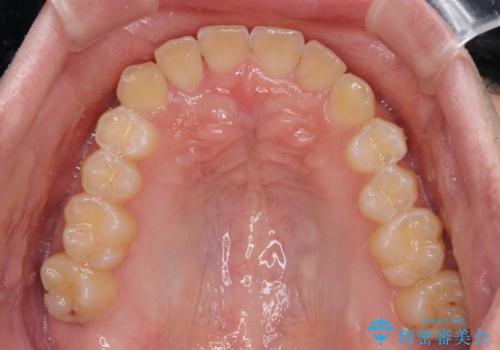

- 前歯のクロスバイトを気にして来院された患者様です。

骨格的には問題がなかったため、インビザラインを用いて咬み合わせを改善していくこととしました。

インビザライン特有の、奥歯の咬み合わせの問題もなく、しっかりと歯列を改善することができました。

舌側転位している上顎側切歯(内側に引っ込んでいる真ん中から2番目の歯)は、インビザラインが最も移動を苦手とする歯であり、これ以上の改善を望まれる場合にはワイヤー矯正、あるいはワイヤー矯正の併用をお勧めいたします。